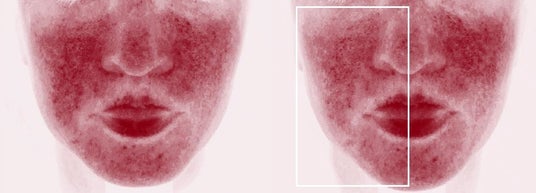

症例1

高周波治療直後 半顔(囲み内)にAIR(アイル)後

上下ともに:機器治療後、半顔だけにAIR(アイル)を20分適用し、前後にヘモグロビン強調画像を撮り検証した。上の症例写真は、右側(向かって左/囲み内)の赤みがより減少、下の写真は、左側の赤み(向かって右/囲み内)がより減少しており、どちらも赤みがより減少したほうがAIR(アイル)を適用した側だった(画像提供:奥謙太郎院長)。

研究デザイン

15名の患者を対象に、マイクロニードル RFもしくはピコ秒アレクサンドライトレーザーを照射後、全顔にフェイシャルパックを行い、半顔のみ微細水粒子「AIR(アイル)」を20分間適用。「AIR」適用側はランダムに割り付け。機器治療前後とフェイシャルパック後、ヘモグロビン強調画像を撮影し、独立評価者が「AIR」適応前後のヘモグロビン強調画像を比較しAIR適応側を正しく同定できるかを検証した。「AIR(アイル)」適用側が正しく同定されたのは15症例中13症例(86.7%)であった。